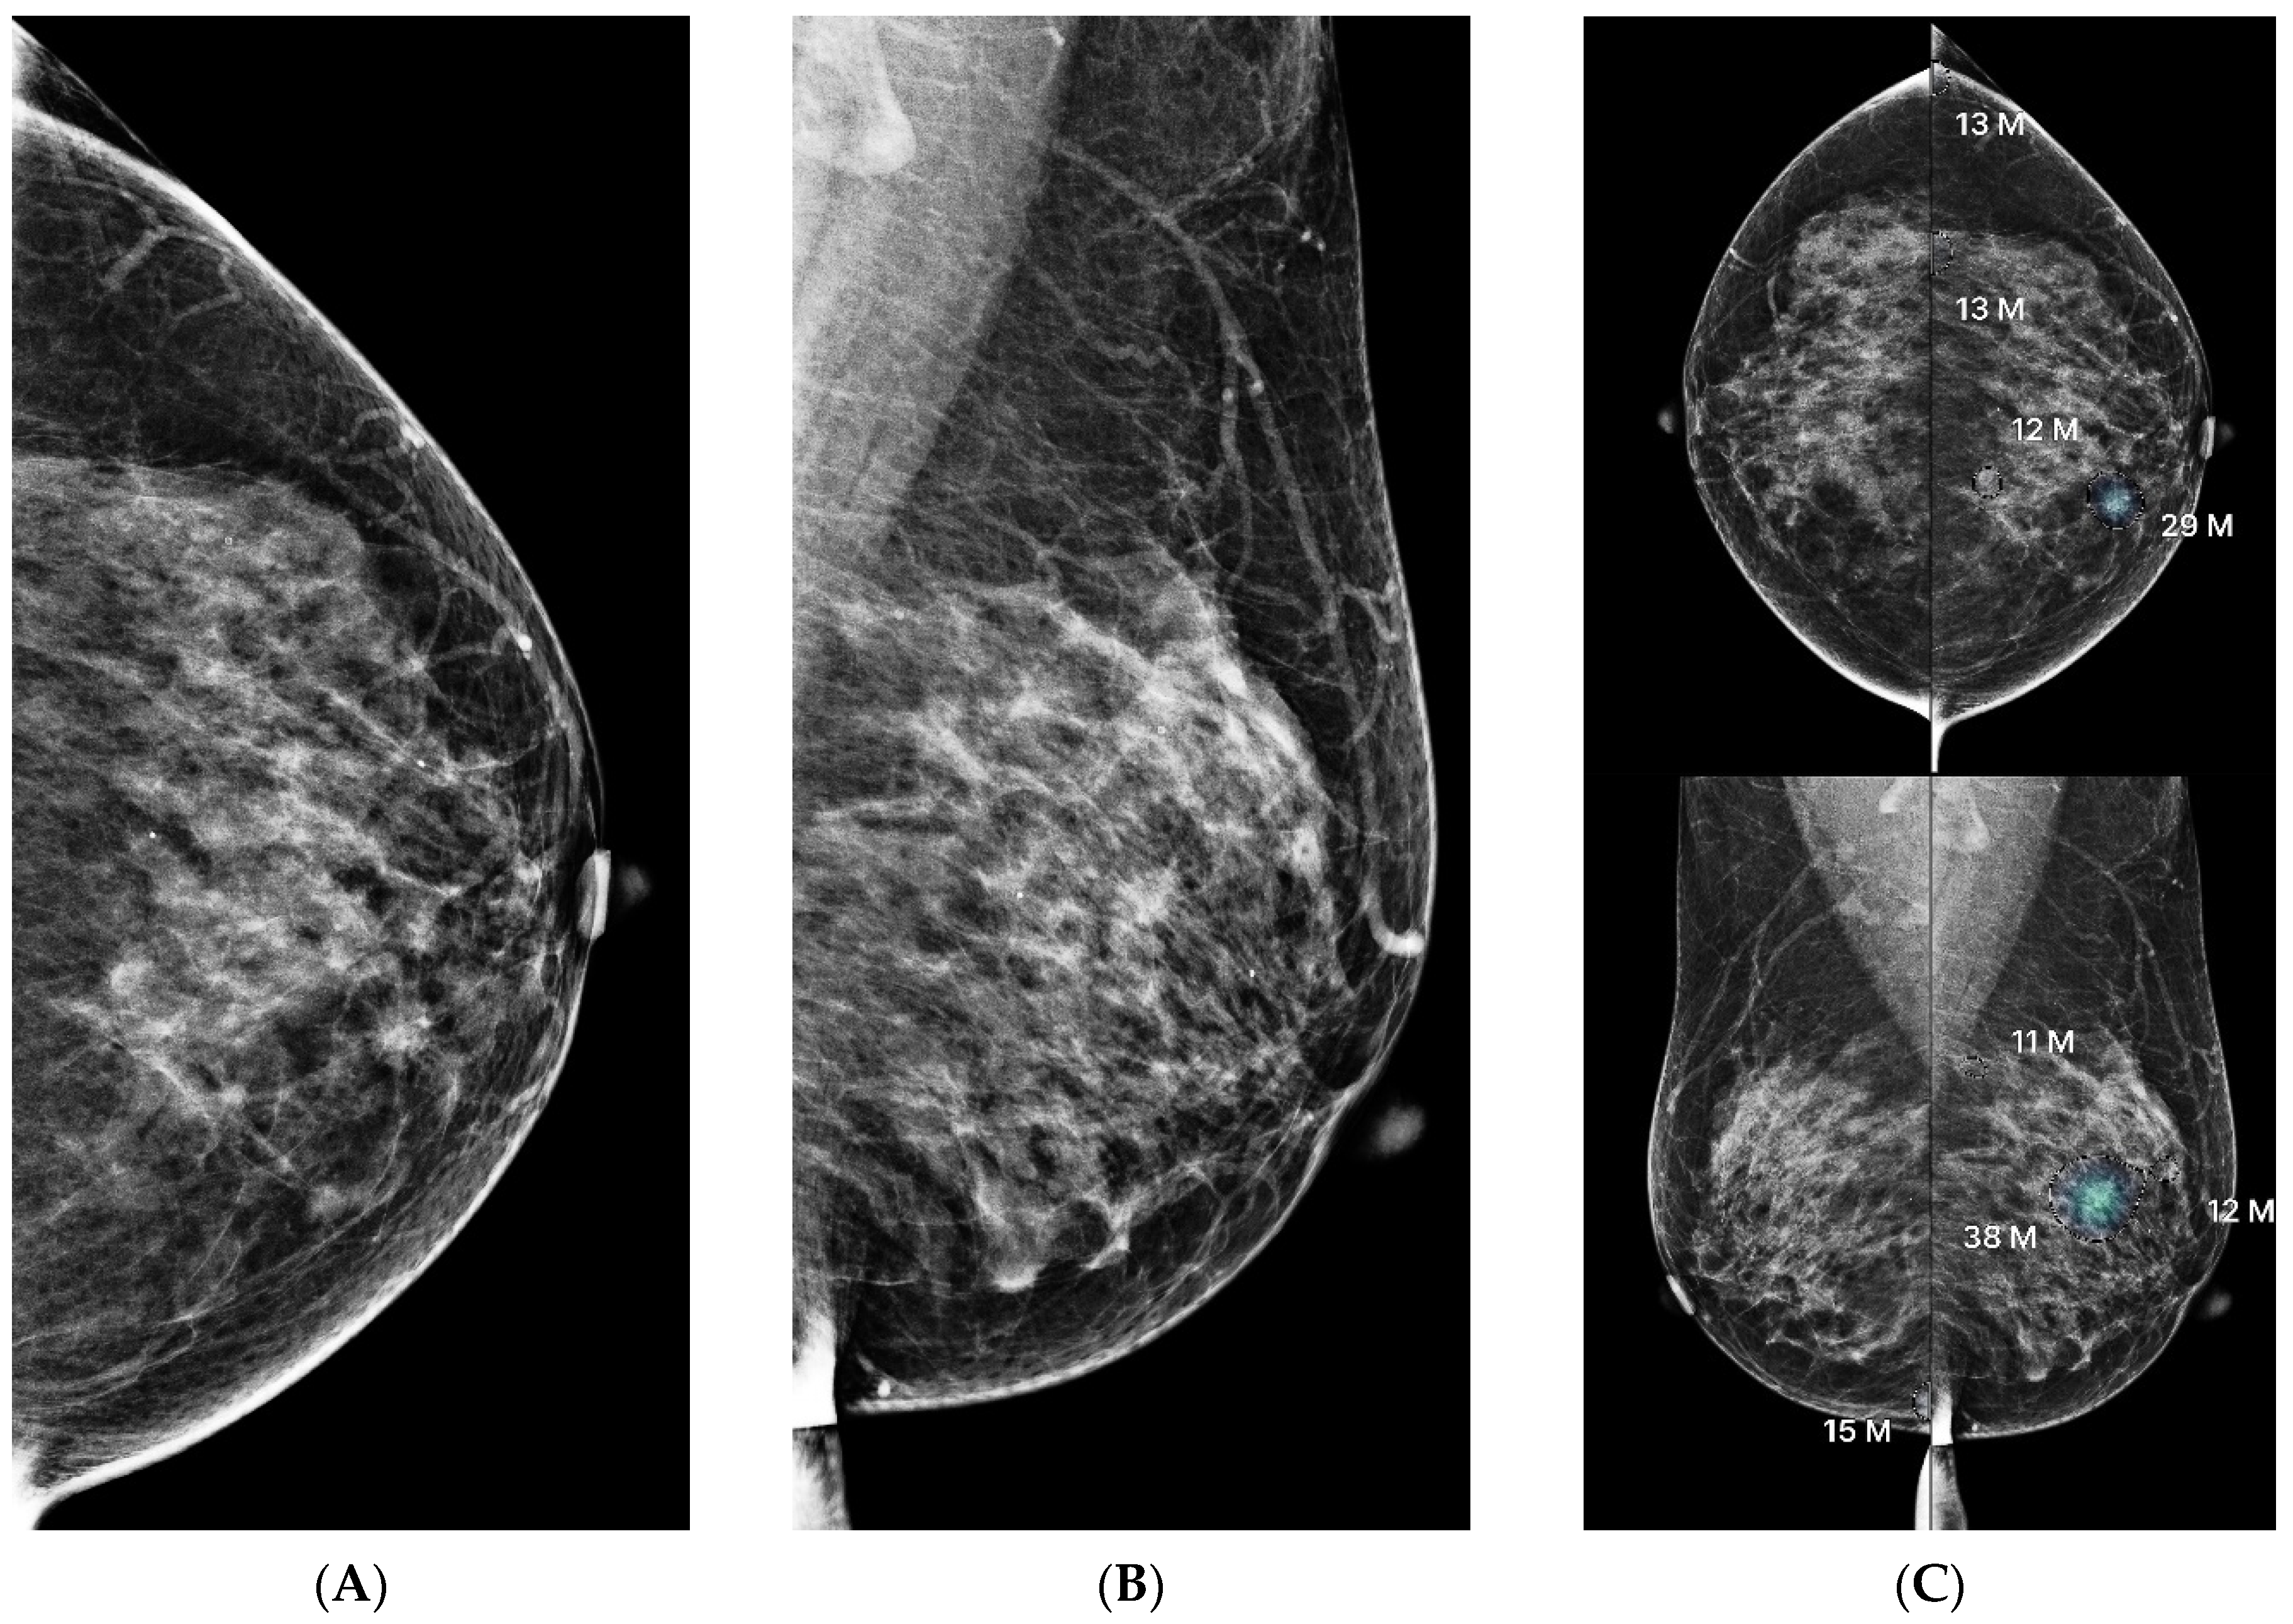

3.3. Lesion Characteristics and AI Score Correlation

3.4. ROC Analysis and Threshold Optimization

3.5. Discordance Analysis Between AI and Radiologists

4. Discussion